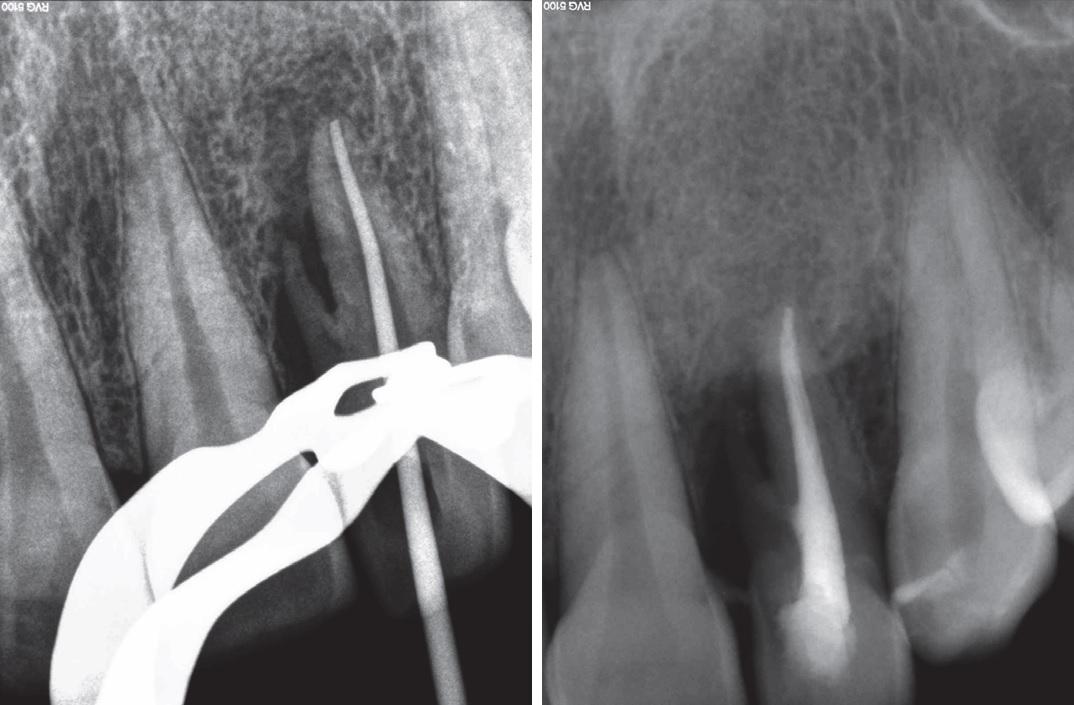

Анатомия: Межкорневая костная перегородка

Раздел: Галерея впечатлений